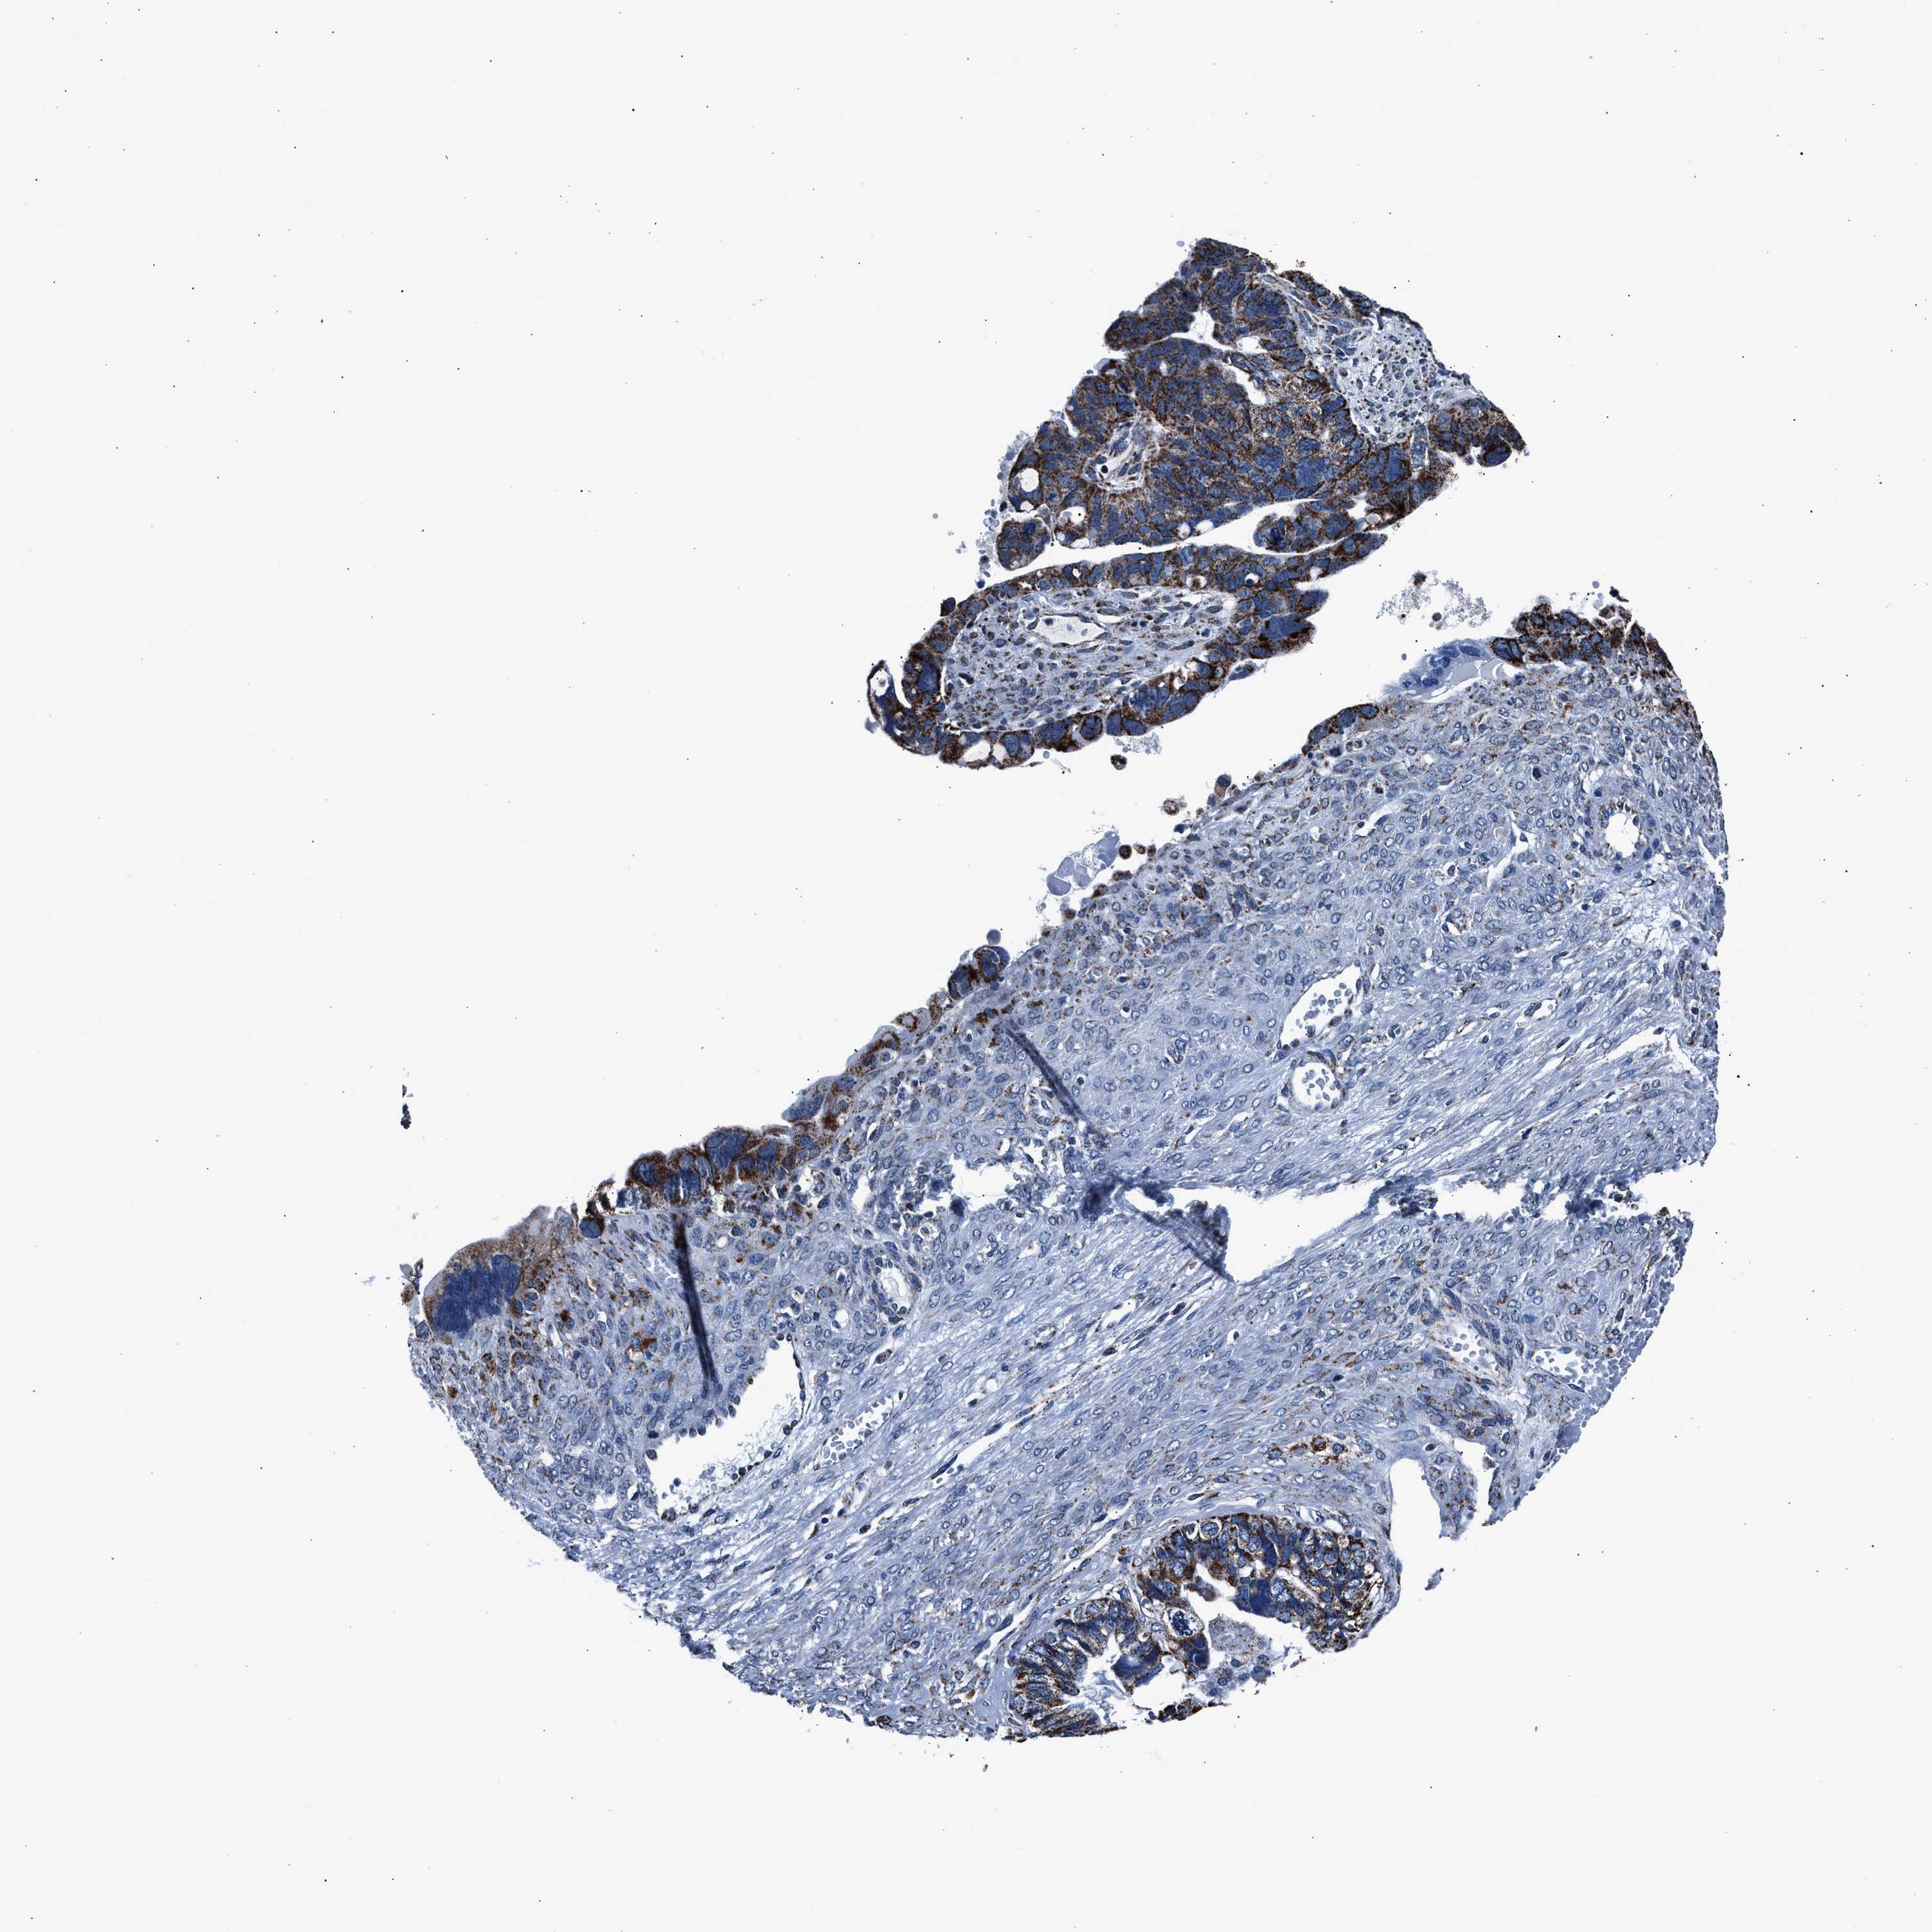

OVARIAN CANCER - Protein expressioni

A mouse-over function shows sample information and annotation data. Click on an image to view it in a full screen mode. Samples can be filtered based on level of antibody staining by selecting one or several of the following categories: high, medium, low and not detected. The assay and annotation is described here.

Note that samples used for immunohistochemistry by the Human Protein Atlas do not correspond to samples in the TCGA dataset.

Antibody stainingi

Antibody staining in the annotated cell types in the current human tissue is reported as not detected, low, medium, or high, based on conventional immunohistochemistry profiling in selected tissues. This score is based on the combination of the staining intensity and fraction of stained cells.

Each image is clickable and will lead to virtual microscopy that enables deeper exploration of all samples and also displays staining intensity scores, fraction scores and subcellular localization as well as patient and tissue information for each sample.

Antibody HPA019522

Antibody HPA021002

Cystadenocarcinoma, serous, NOS

Carcinoma, endometroid

Cystadenocarcinoma, mucinous, NOS

Carcinoma, NOS